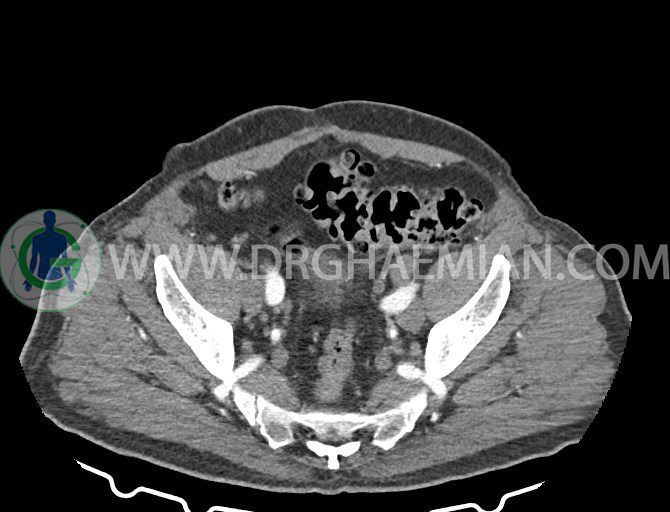

سی تی اسکن لگن یکی از روش های تصویربرداری با سی تی اسکن است. این روش با استفاده از تشعشعات تصاویر عرضی از ناحیه شکمی ایجاد میکند. در این کیس ديورتيكولوزيس، کیست های کورتیکال در هر دو کلیه، لنفادنوپاتی، کلسیفیکاسیون دیواره آئورت و شریان ایلیاک، تغییرات DJD ناحیه توراکولومبار و پروستات بزرگتر از عادی دیده می شود.

در سي تي اسکن اسپيرال شکم و لگن با و بدون کنتراست خوراکی و وريدی (مولتي ديدکتور 16 با مقاطع ظريف و بازسازي هاي ساژيتال و کرونال):

– کلسيفيکاسيون ديواره آئورت و شريان ها ايلياک همراه با نشانه هاي ترومبوز مورال در بيفورکاسيون ائورت با امتداد به پروگزيمال هاي شريان هاي ايلياک

– ديورتيكولوزيس در کولون نزولي وسيگموئيد

لنفادنوپاتي به ابعاد mm 22 x 25 مجاور شريان ايلياک خارجي چپ و به ابعاد mm 17 x 28 مجاور شريان ايلياک خارجي راست

– پروستات به ابعاد mm 45 x 54، بزرگ تر از نرمال

مشهود است.